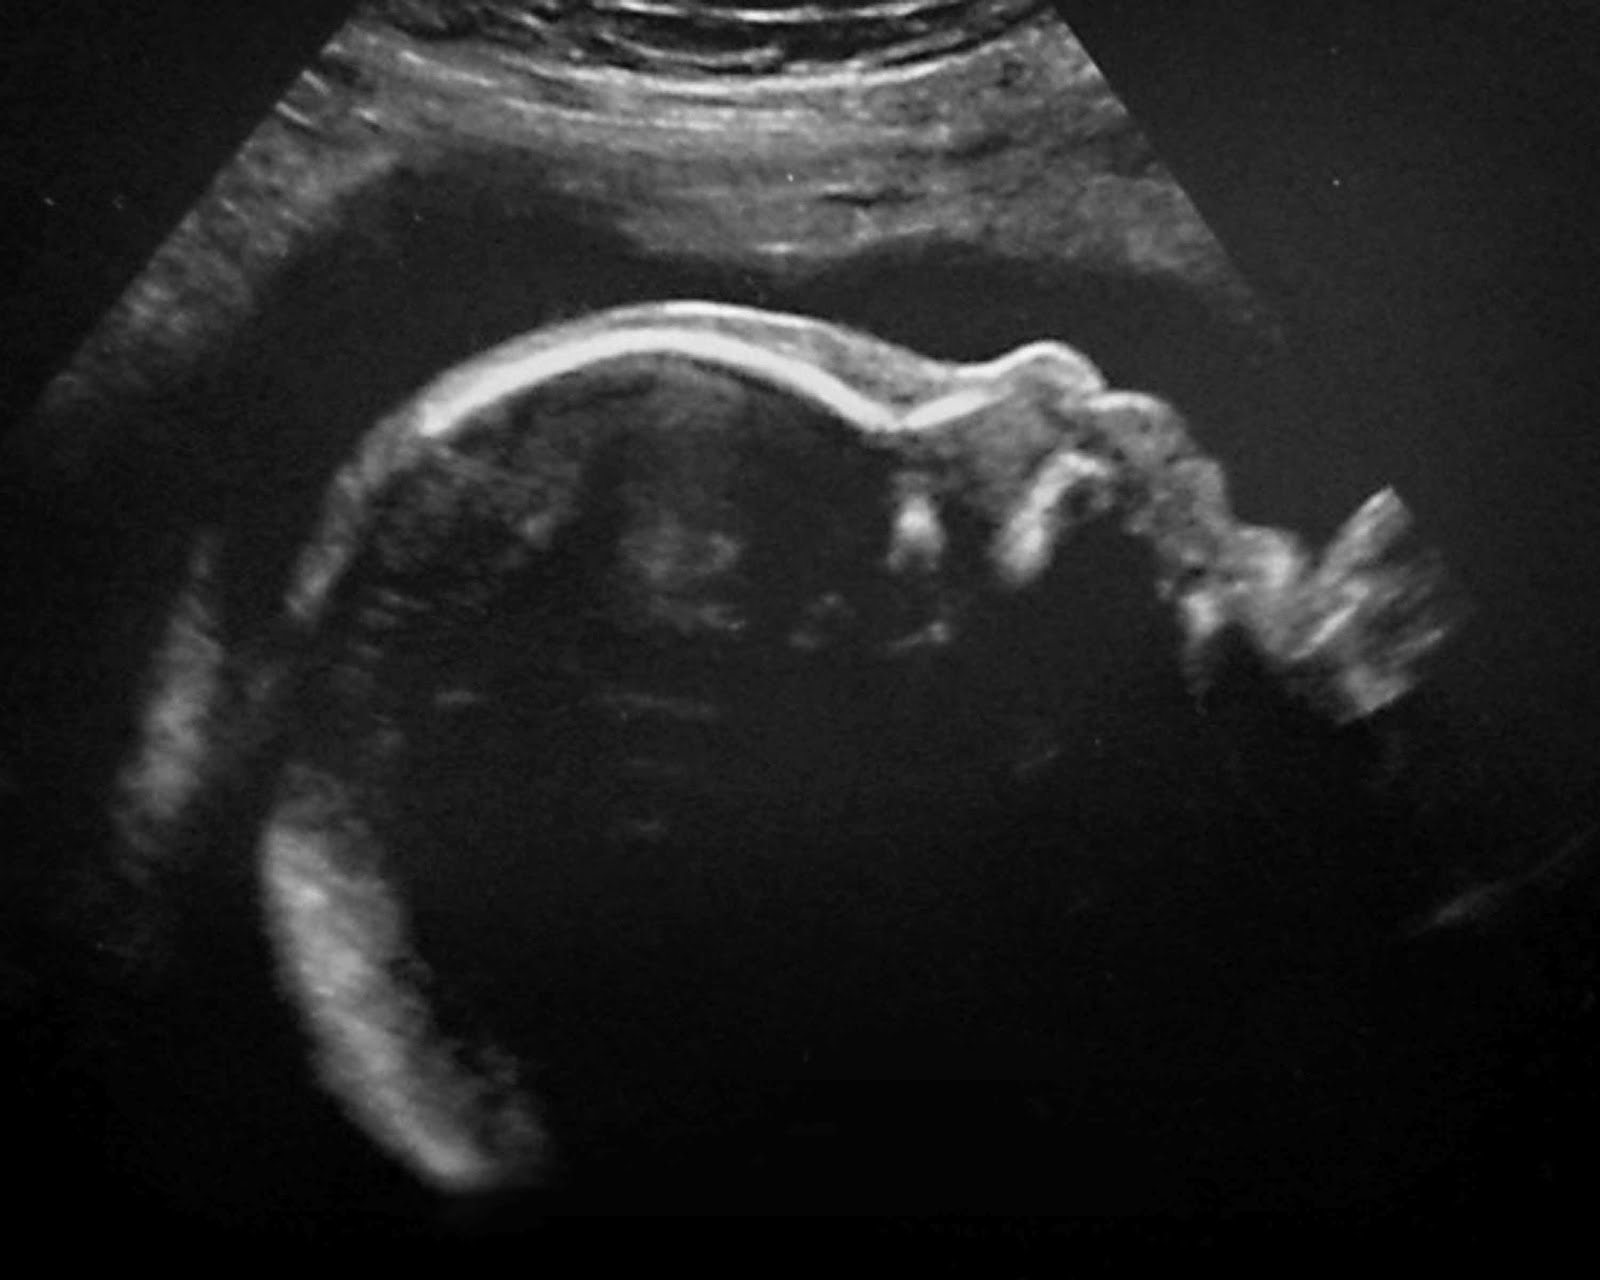

On Friday April 6, 2012 our lives changed forever. I was asked to come in for my 3rd ultrasound to check a few things they couldn't see at my 20 week scan. When I went in for my 20 week scan they were unable to see the back of the baby's brain and they reassured me that it was just the way he was laying. They told me everything else on the baby looked great and he was growing healthy. I then went home and told myself everything was fine and not to worry. I returned to the doctor 4 weeks later for a routine check up and everything went great. She went over the ultrasound and told me that he looked very healthy and was growing very well. She then told me to set up another ultrasound appointment to get another look at the part of his brain that they were unable to see. The ultrasound tech told me to come in the next day at 3:30. I returned the next day and waited nervously in the waiting room, telling myself that everything was fine. When I was finally called back I laid back on the table and watched as she scanned over the baby. It didn't take me long to figure out that there was something wrong. The ultrasound tech kept scanning back and forth and didn't say a word for what seemed like a life time. I finally looked at her and asked if there was something wrong. She said she was still unable to see the cerebellum (the back of the baby's brain) and that she didn't think it was because of the way he was laying. My heart dropped...I couldn't think straight, and I felt as if I was in another world. It's hard to explain the way I was feeling...it was a nightmare. I fought back the tears as she scanned over the rest of his body. She told me that there were a few other things that she was seeing but was not able to tell me a lot of information about it. She said that there was a problem with his spine and that it didn't look good, she then told me that it looked like there was a hole in his abdomen and it looked as if there was something wrong with his feet. I didn't know what to think at that point, I just kept asking questions that she said she couldn't answer for me. I felt so angry that she wouldn't tell me more than what she was. She told me that I would have to talk to my doctor about everything and that she was so sorry for the bad news. She told me that the baby could still live but the chances weren't very good. She then took me into another room and told me to wait there so she could call my doctor and let her know what was going on. That's when I completely lost it, I called Joe hysterical and told him that he needed to get to the doctors office right away, things weren't looking good. When he got there he was of course hysterical and I told him everything that was going on. After a few minutes the tech came back and told us that she couldn't get a hold of our doctor but she left a message. She also told us that she made us an appointment with a specialist for Monday afternoon in Salt Lake. She said she would have a doctor call us as soon as she got a hold of her and that we were able to go home. So after spending the longest most horrible Easter weekend we have ever had we finally made it to the specialist. They took another ultrasound and that's when we learned that our little Crue had a sever case of spina bifida. The tech then went over the rest of his little body and said that there was no hole in his abdomen and that he did in deed have a cerebellum. He said the cerebellum was hard to see because it was being pulled down by his spine and was being pressed up against the back of his skull. He then told us that our boy had a very good chance of surviving but he may never be able to walk. We were also told that he had bi lateral clubbed feet (clubbed feet are when the baby's feet are turned inward) but that could be fixed with physical therapy or surgery. We were relieved to know that he would live but devastated to hear that he may never walk. He explained to us all of the possible side effects and everything to expect when having a baby with Spina Bifida. I can't even begin to explain to you the emotion or the heartache that i felt at that moment. He told us that we would deliver the baby C section at 39 weeks and that he would go in for surgery to close the hole in his back within the first 24 hours of his life. He would then have to have surgery to have a shunt put in his brain to drain the extra fluid that builds up from the pressure the spine causes. Our lives have been forever changed and as hard and emotional as this has been, we are trying to keep our heads up and hope for the best. We pray every day and night that Crue will have the best possible out come that he can have. I don't know where I would be without the gospel and the church in my life. As hard as it is to except at times I believe that the lord has sent us this special little boy for a reason and that we are being blessed in so many ways, even if we can't see that right now. One thing that has helped us cope with this is a talk that was given by Ronald A. Rasband at general conference. Here's a link if would like to read it. It was an amazing and uplifting talk. http://www.lds.org/general-conference/2012/04/special-lessons?lang=eng We just want to thank all of our family and friends for all the love and support. We are truly grateful for everything that everyone has done for us. All we ask is that you keep praying for our sweet baby boy.